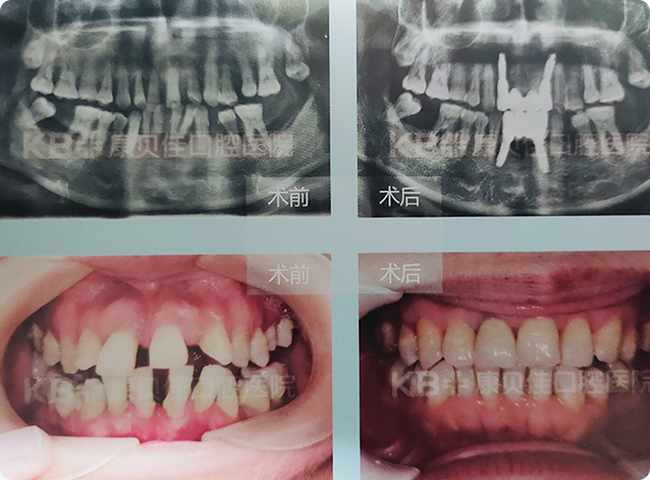

郭先生 60岁

5年前牙齿开始松动、脱落,直到上半口掉光,下半口仅剩的几颗牙也摇摇欲坠,没有办法保留。为提高生活质量到康贝佳拔除松动牙,采用种植4颗技术恢复了上半口牙,下半口采用“缺多种少”方案恢复。

治疗方案:

杆卡 上颌种植4颗 杆卡 下颌种植3颗